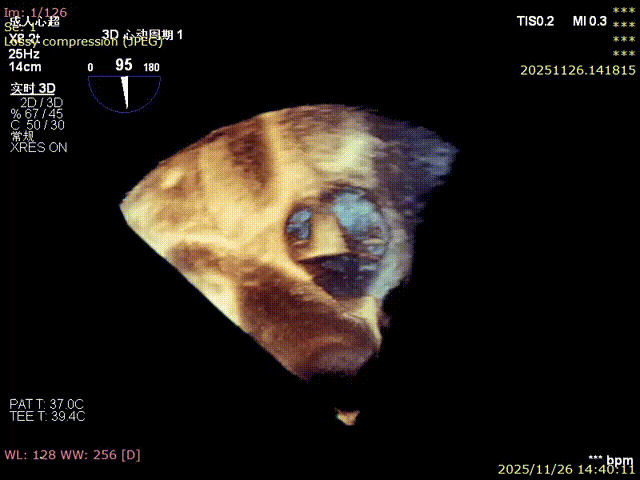

3D image

Annulus area: 16.2 cm²